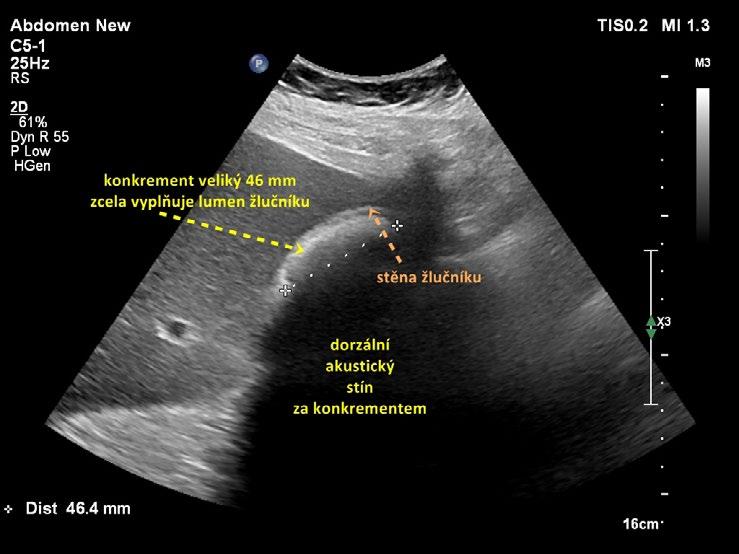

• vyplnění celého lumen objemným konkrementem (obr. 1.16). Do značné míry podobný obraz však vytváří plyn v hepatální flexuře tračníku (obr. 1.17). Pro alternativu objemného konkrementu je zásadní identifikace jeho hladkého povrchu a zobrazení stěny žlučníku;

Obr. 1.16 Objemná cholecystolitiáza